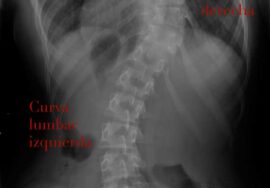

يعاني العديد من الأطفال والمراهقين المصابين بالجنف، أو اعوجاج العمود الفقري، من الألم، ضعف التوازن، وصعوبة الحفاظ على الوضعية الصحيحة للجسم. لذلك، يتساءل الكثير من الأهل: ما هي أفضل التمارين التي تساعد طفلي؟ وهل يمكنها تخفيف الألم وتحسين الوضعية؟ في هذا الدليل المبسّط، سنوضح أفضل 10 تمارين وتمارين تمدد لتقوية العضلات، تحسين المرونة، وتخفيف الألم بطريقة آمنة، مع شرح كيفية تنفيذها للأطفال تحت إشراف الأهل والأخصائي.

ما أهمية التمارين لمرضى الجنف؟

أولًا، يجب أن نفهم أن التمارين والتمدد لا تعالج الانحناء بالكامل، لكنها تلعب دورًا مهمًا في دعم صحة العمود الفقري. على سبيل المثال: